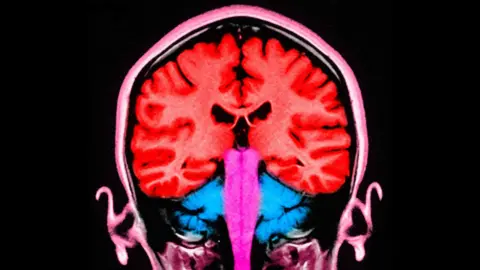

Scientists have discovered how to make people less selfish – at least temporarily – by stimulating two areas of their brain.

During the experiment, an electrical current was applied to the frontal and parietal areas of the brain – situated at the front and towards the back. When these areas were stimulated at the same time, the participants gave away more money.

In that study, the researchers pinpointed the two brain areas that appeared to be “talking to each other” – with brain cells firing at the same frequency – when players gave away more money.

Those two brain areas are known to play a role in decision-making and in empathy, or distinguishing the feelings of others from our own.